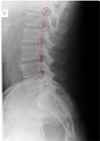

LATERAL THORACIC LANDMARKS lateral thoracic view

disc spaces

108

Lateral thoracic view

endplate tips